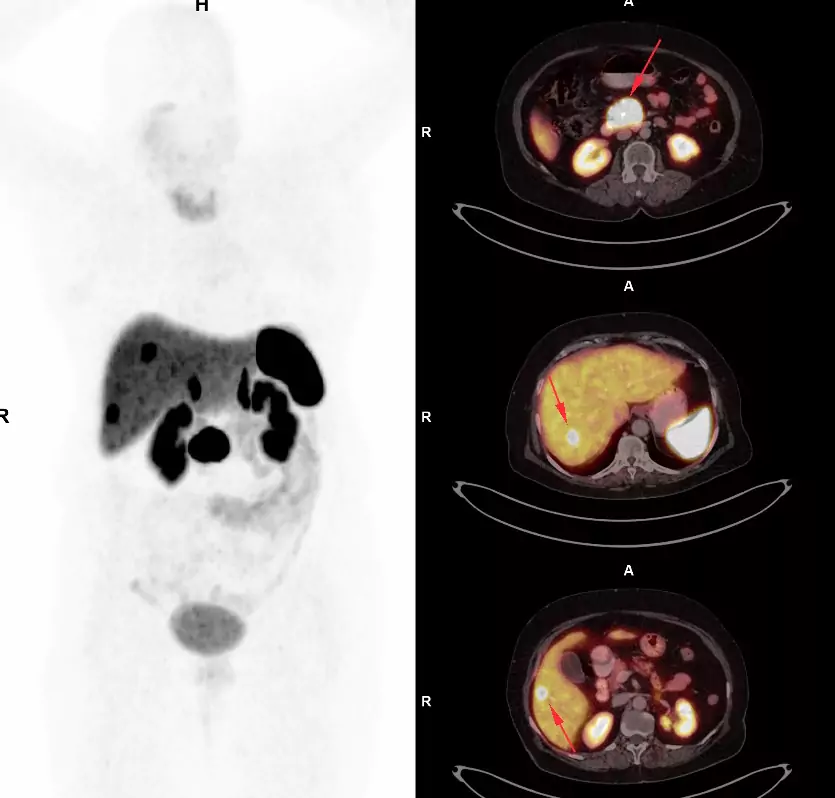

PET (Position Emission Tomography) is a nuclear medicine technique for evaluating biomedical and physiological processes in the body.

The combination with CT scan adds anatomic information.

68Ga labelled DOTATOC is readily available with our in house gallium generator for evaluation of neuroendocrine tumor's at various stages in the disease process.